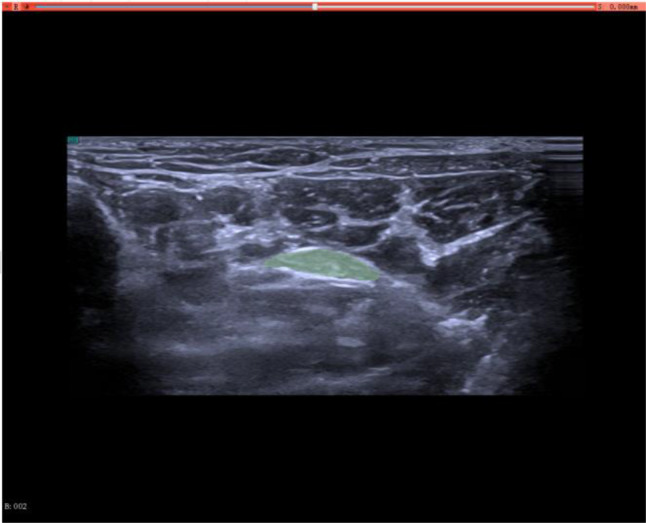

Development and validation of a nomogram for diabetic tibial neuropathy based on ultrasound radiomics: a multicenter study.

基于超声放射组学的糖尿病胫骨神经病变nomographic的发展和验证:一项多中心研究。